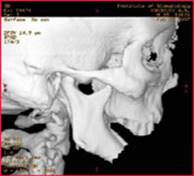

Лор-врачи после обзорных снимков очень любят назначать зонограммы (Рис. 1.) и томограммы (Рис. 2 а, б.) лицевого черепа. Это позволяет выделить интересующую область (например, пазухи) для детального осмотра. Есть даже гайморография – искусственное контрастирование гайморовых пазух. Востребована и у Лор-врачей и КТ. Ведь компьютерная томография чрезвычайно информативна.

Зонограмма средней зоны пациента с грубой деформацией лицевого черепа: гипертелоризмом, пороком формирования полости носа.

СК томограмма пациента с дефектом нижней челюсти после огнестрельного ранения (а), моделирование замещения дефекта аутотрансплантатом из малоберцовой кости по данным СКТ (б)